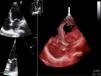

Monitorizada em ambiente de unidade de cuidados intensivos cardíacos, realizou ecocardiograma, que revelou ventrículo esquerdo de dimensões normais com fracção de ejecção do ventrículo esquerdo (FEVE) global ligeiramente deprimida (FEVE ± 45%) e imagens compatíveis com VENC a nível apical (trabeculações exuberantes com relação camada trabeculada/não trabeculada superior a dois e com fluxo detetado por Doppler de cor ao nível das mesmas) (Figuras 4 e 5). Foi efetuada coronariografia, revelando ausência de doença coronária.